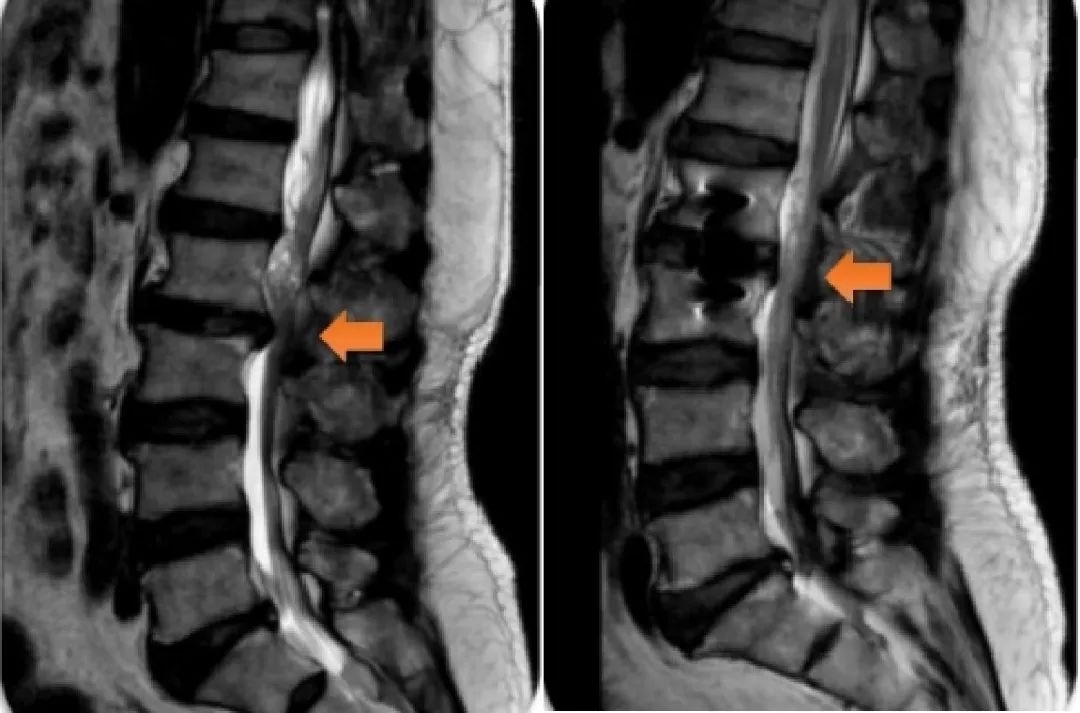

患者手术前后影像检查图,橙色箭头为颈椎狭窄处

经过仔细询问病史,这位患者常年伏案工作,近年来常感颈部不适。再一查体,病理反射很明显,医生初步考虑不是脑梗,而是颈椎问题。再经过颈椎MRI检查,最终明确诊断为脊髓型颈椎病,建议住院手术治疗。

医生介绍说,脊髓型颈椎病是最严重的一种颈椎病,由于椎管变窄,压迫到脊髓,再加上保护脊髓、缓冲脊髓运动的脑脊液也变少,在突然的外力作用下,颈部脊髓容易损伤。它占全部颈椎病的10%~15%,虽然发病率不高,但它在颈椎病的各种类型中却是危害最大的——起病隐匿,致残率高。